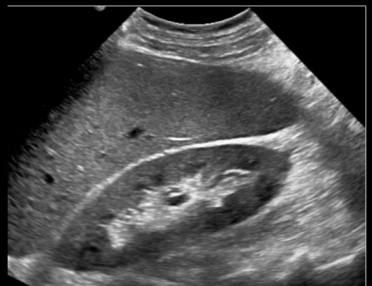

10

Q

A

Muy blanco y con textura gruesa en margenes

Cirrosis